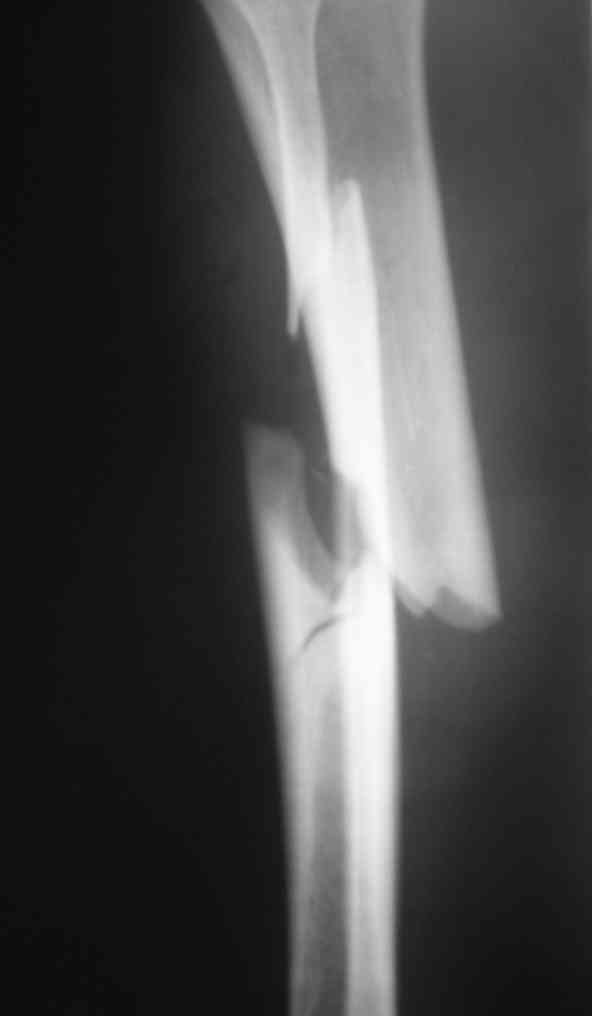

Вчера первый раз синтезировали голень гвоздем Fixion.

Спиральный оскольчатый перелом, ниже середины, у молодого парня. Сделали "классический" вариант гвоздя, который еще без винтов. Получилось все легко. Не торопясь, сделали операцию минут за 20. См. фото.